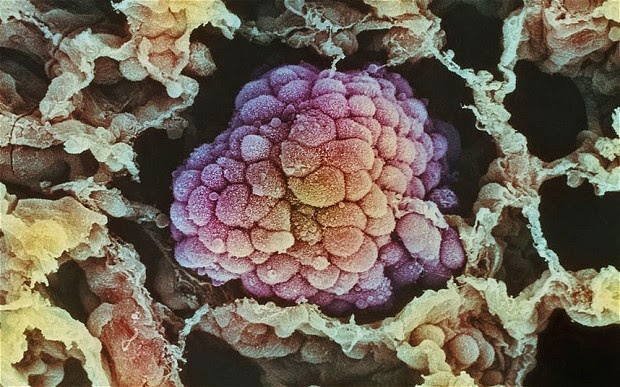

Ο καρκίνος είναι μια ασθένεια των κυττάρων, τα οποία είναι βασικά δομικά στοιχεία του σώματος. Το σώμα μας φτιάχνει συνεχώς νέα κύτταρα για να μας βοηθήσει να αναπτυχθούμε, να αντικαταστήσουμε φθαρμένα κύτταρα, ή να θεραπεύσουμε τα κατεστραμμένα κύτταρα μετά από έναν τραυματισμό.

Στις περισσότερες περιπτώσεις, η μετάλλαξη είναι ακίνδυνη. Παρ’ όλα αυτά, σε μερικές περιπτώσεις, το κύτταρο αποτυγχάνει να διορθώσει το λάθος και η μετάλλαξη οδηγεί σε ανάπτυξη όγκου – σε ανεξέλεγκτη ανάπτυξη του καρκίνου.

Κατεστραμμένα γονίδια είναι δυνατόν να αναγκάσουν τα κύτταρα να συμπεριφέρονται αφύσικα. Μπορεί να πάρουν τη μορφή εξογκώματος που ονομάζεται “όγκος”.

Οι όγκοι μπορεί να είναι καλοήθεις (όχι καρκίνος) ή κακοήθεις (καρκίνος). Οι καλοήθεις όγκοι δεν εξαπλώνονται πέρα από τα συνήθη όριά τους σε άλλα μέρη του σώματος.

Όταν ένας κακοήθης όγκος αναπτύσσεται για πρώτη φορά, ίσως να περιοριστεί στην αρχική του περιοχή. Αν δεν αντιμετωπιστούν αυτά τα κύτταρα, είναι δυνατόν να εξαπλωθούν πέρα από τα κανονικά όριά τους και σε περιβάλλοντες ιστούς, κι έτσι να εξελιχθούν σε διηθητικό καρκίνο.

Για να γίνει ένα καρκινικός όγκος μεγαλύτερος από το κεφάλι μιας καρφίτσας, πρέπει να αναπτύξει τα δικά του αιμοφόρα αγγεία. Μερικές φορές, κάποια κύτταρα απομακρύνονται από τον αρχικό (πρωτοπαθή) καρκίνο, είτε μέσα από τα κανάλια των υγρών των τοπικών ιστών ή με την κυκλοφορία του αίματος, και εισβάλουν σε άλλα όργανα. Όταν τα κύτταρα αυτά φτάσουν σε μια νέα τοποθεσία, μπορεί να συνεχίσουν να αναπτύσσονται και ίσως δημιουργήσουν άλλον έναν όγκο σε αυτή την περιοχή. Αυτό ονομάζεται δευτερογενής καρκίνος ή μετάσταση.

Καρκίνος είναι η μετάλλαξη ή το σύνολο των μεταλλάξεων που συμβαίνει στο DNA του κυττάρου και ειδικότερα στα γονίδια που είναι υπεύθυνα για της ισορροπία μεταξύ της φυσιολογικής ανάπτυξης και της απόπτωσης (θάνατο) του κυττάρου. Με τον τρόπο αυτό το φυσιολογικό κύτταρο μετατρέπεται σε ένα «αθάνατο» κύτταρο με επιθετική και διηθητική διάθεση έναντι των υπόλοιπων φυσιολογικών κυττάρων.